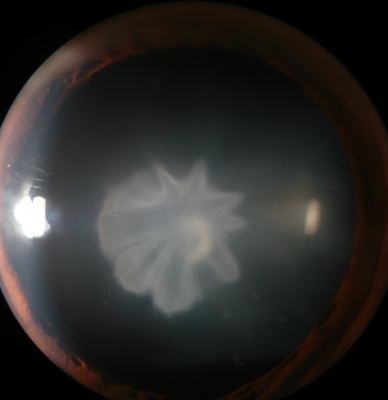

Posterior Subcapsular Cataract

Etiology

Posterior subcapsular cataracts (PSC) are opacities located in the most posterior cortical layer, directly under the lens capsule. This type of cataract tends to occur in younger patients compared to cortical or nuclear sclerotic cataracts. Progression is variable but tends to occur more rapidly than in nuclear sclerosis. Thus, PSC can reduce visual acuity earlier and quicker than its more common nuclear or cortical cataract counterparts. Equatorial and posterior cortical degeneration during PSC formation leads to posterior migration, inward displacement, and equatorial lens epithelial cell (LEC) malformations. During this aberrant migration of equatorial LECs to the posterior pole, many cells take on a characteristic ballooned or swollen bladder-like shape, first described by pathologist Carl Wedl. Accumulation of these dysplastic, nucleated, bladder cells, or Wedl cells, begins as a focal dot-like area in the posterior cortex, proceeding into granular opacities in the posterior pupillary zone of the lens, and in advanced cases, ultimately growing denser into a large, white, granular, vacuolar plaque. On slit-lamp examination, these opacified, granular plaques can appear similarly to posteriorly migrating Elschnig pearl formations postcataract. Histologically, Wedl cells are described by their scarce organelles, crystalline proteins, prominent cytoskeleton, and degenerating nuclei.

The exact mechanisms behind the pathologic migration or Wedl cell generation are not fully understood, although ionic uncoupling pathways, oxidative stress, and interleukin-induced LEC activation have all been suggested to play a role in pathogenesis. Risk factors for PSC and Wedl cell pathology include but are not limited to calcium imbalance, atopy, ionizing radiation, high or prolonged use of glucocorticoids, diabetes, myopia, ocular inflammation (uveitis), and vitrectomy. These Wedl cell aggregations, a signature hallmark of all PSC development, cause decreased visual acuity and contrast sensitivity. Symptoms include glare and difficulty seeing in bright light, and near vision is often more affected than distance.

Symptoms

- Glare

- Difficulty with near greater than distance vision (typically, but many patients may notice the opposite)

- Often rapidly diminishing vision